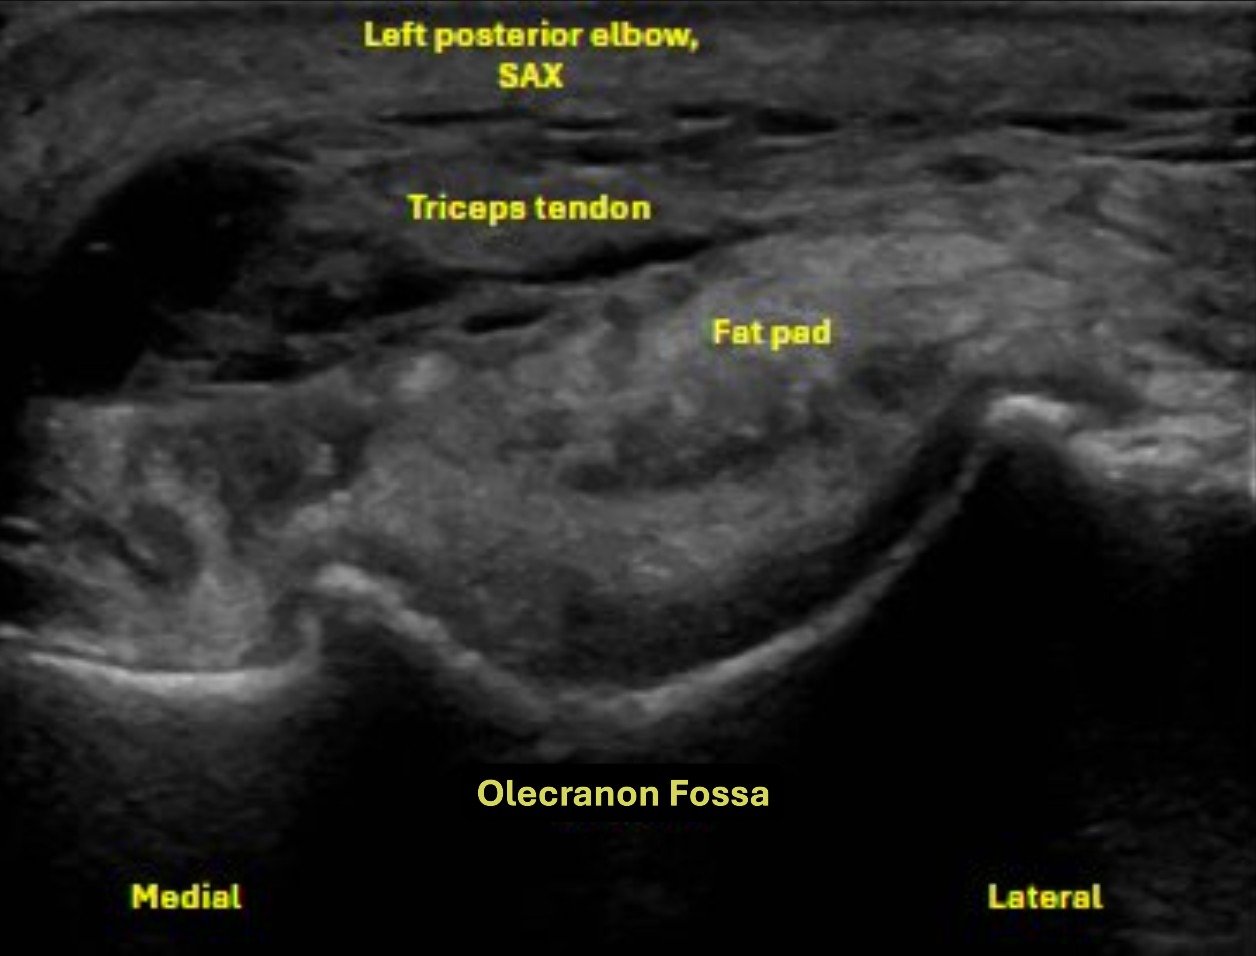

Short axis view at the level of the distal humerus, evaluating the triceps tendon/muscle, posterior fat pad, and olecranon fossa

Labeled short axis view of the distal triceps tendon stump showing loss of normal fibrillar structure of the triceps tendon, with discrete bony avulsions within the retracted triceps tendon. There is anechoic and hypoechoic fluid signal, compatible with hematoma or seroma formation.

There is disruption of the distal triceps tendon fibers at the olecranon process, characterized by a hypoechoic defect and loss of normal fibrillar architecture at the tendon insertion, consistent with a distal tendon rupture. The proximal tendon stump appears retracted with intervening anechoic and hypoechoic fluid signal, compatible with hematoma or seroma formation. The olecranon bursa shows mild reactive fluid distention.